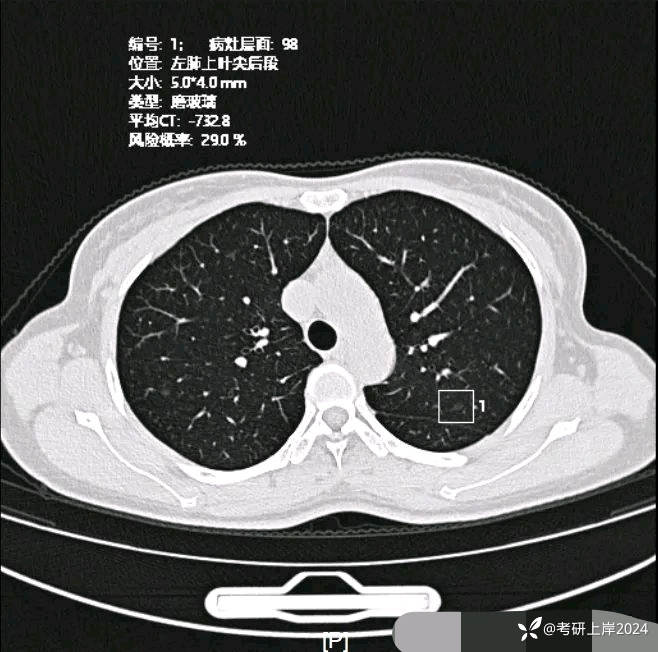

患者最近的检查有AI辅助诊断意见,找出的病灶分别如下:

病灶7:左上叶微小淡磨玻璃结节,考虑少许慢性炎或伴肺泡上皮增生可能性较大;